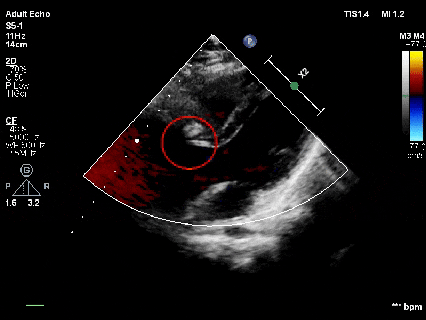

释放前超声

释放前超声下封堵器型态良好,骑跨室间隔两侧

释放后超声

超声下可见室水平和房水平都无残余分流